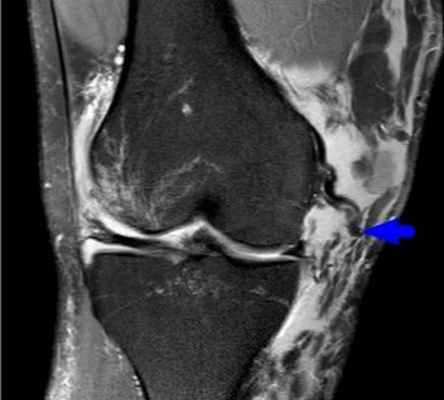

Диагностика кисты Беккера

Рентгологическое исследование, к сожалению, не может выявить кисту, поэтому.

Основным, самым доступным методом является ультразвуковая диагностика сустава и/или мягких тканей сустава. Она позволяет уточнить размеры и структуру кисты.

Также кисту можно выявить при проведении МРТ коленных суставов. ️